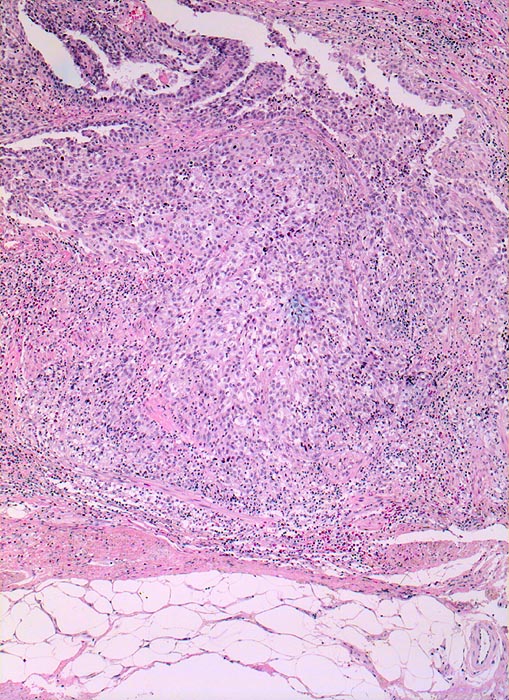

Morphologische Merkmale:

• Multiple Fragmente einer transurethralen Resektion.

• In der Mitte oben ist ein Harnblasenfragment mit tumorfreien Anteilen der Harnblasenwandmuskulatur erkennbar. Dieses Fragment ist bedeckt von einem aus wenigen Zellagen bestehenden dyskohäsiven Urothel, von dem sich einzelne Zellen ablösen. Die Zellkerne sind pleomorph, hyperchromatisch und vergrössert(Carcinoma in situ des tumorfernen Urothels).

• Fragmente eines papillär aufgebauten Karzinoms.

• Tumorzellkerne mit ausgeprägter Pleomorphie und Hyperchromasie sowie prominenten Nukleolen. Fehlende polare Ausrichtung der Tumorzellen. Zahlreiche Mitosen und Apoptosen.

• Kleinherdige Tumornekrosen.

• Invasion der Lamina propria (Tumorfragmente links): Kleine Tumorzellgruppen oder Einzelzellen haben die Basalmembran an wenigen Stellen durchbrochen und liegen in der Lamina propria.

• Begleitendes dichtes gemischtes Entzündungsinfiltrat.